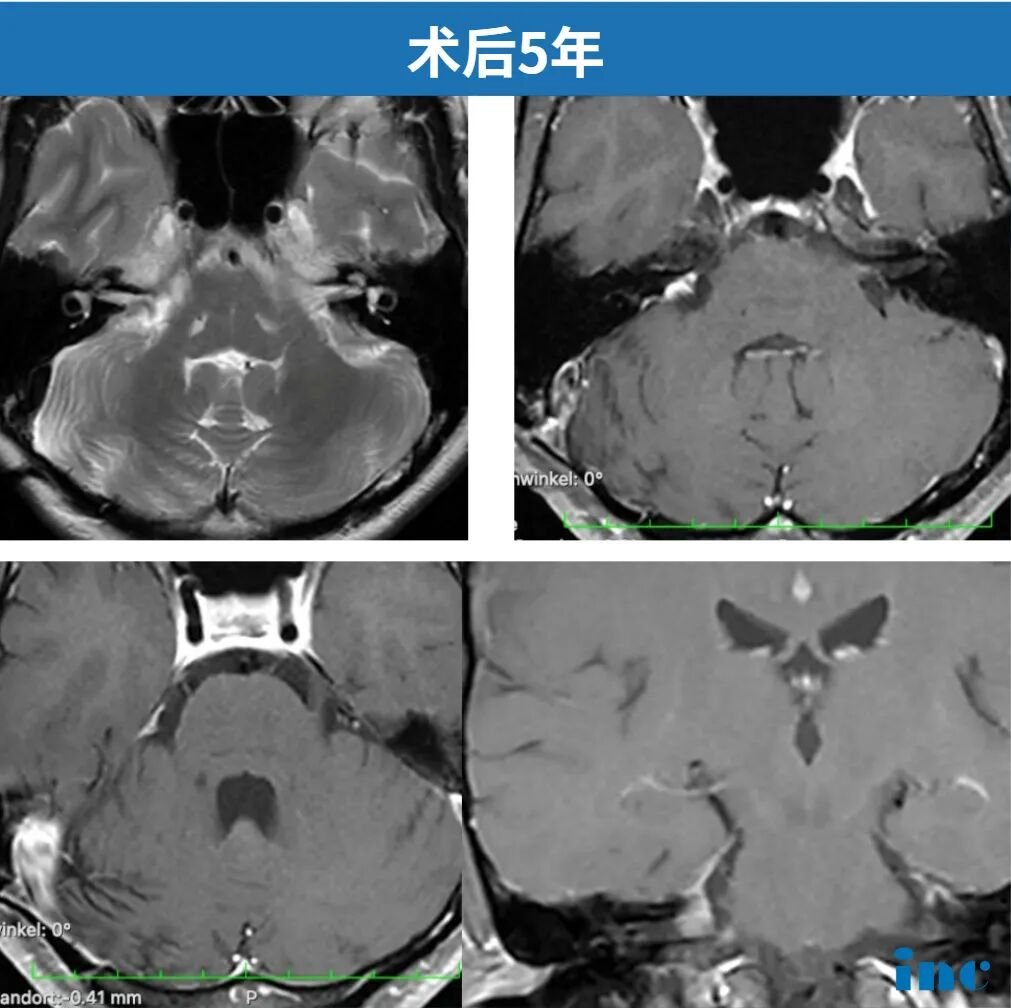

术后虽有短暂面瘫但也得到恢复,如今五年复查,核磁显示“非常理想”,无残留无复发。正常生活和工作……